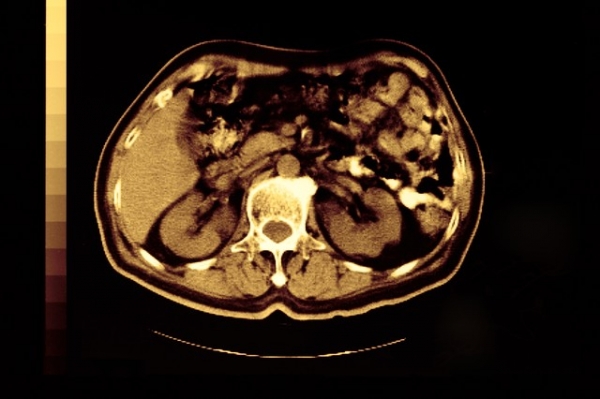

对于有家族史的人群,建议进行基因检测和定期筛查,比如通过磁共振成像(MRI)或内镜超声(EUS)监测胰腺健康。